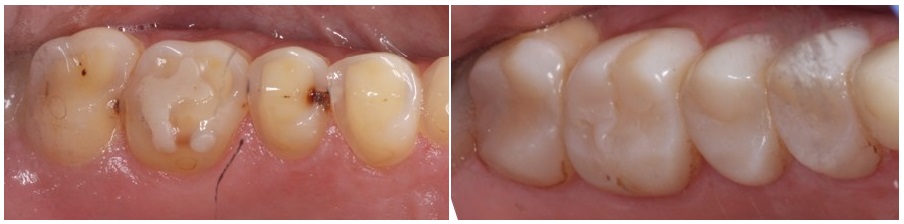

On a letter stage we started changing the composite build ups, with all ceramic restorations made out of e-max porcelain.

Some of them were covering only the occlusal surfaces of the teeth, while others were covering the buccal sides too, meeting the esthetic demands of our petient.

The following pictures present the occlusal surfaces of the maxillary and mandibuler teeth, before and after the cementation of our aditive restorations.